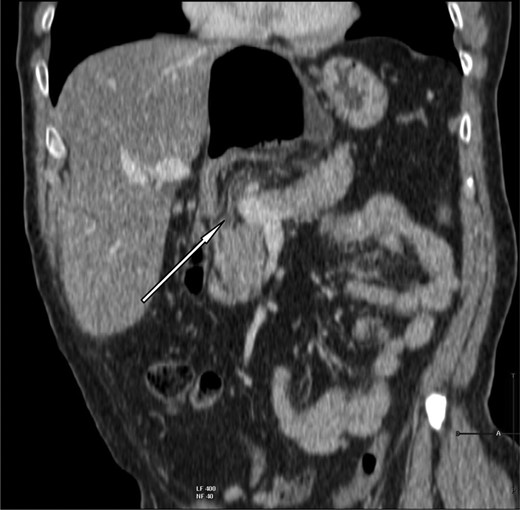

A 69-year-old patient presented to our emergency room with progressive dull abdominal pain and distension without nausea, vomiting or change in bowel habits. Physical examination showed pain with moderate guarding in the right upper and lower quadrants. A plain abdominal X-ray and a CT scan were performed. Radiological findings suggested the diagnosis of an internal hernia through the epiploic foramen and containing the right colon with important distension of the caecum (Fig. 1). Surgical exploration was then performed using an open approach. At laparotomy, we found an internal herniation of the caecum and the entire ascending colon through the foramen of Winslow (Figs 2 and 3). After hernia reduction, multiple patchy areas of caecal necrosis were observed (Fig. 4). A formal right hemi-colectomy was therefore performed. The postoperative recovery was uneventful.

Coronal slice showing herniation of right colon through the foramen of Winslow.